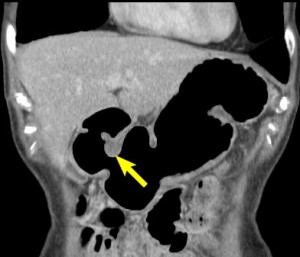

In recognition of awareness for these diseases, I want to highlight several specialized radiological methods offered at UCSF. These methods are geared toward non-invasive imaging of the stomach and esophagus. These imaging procedures utilize oral effervescent granules, which naturally form a small amount of carbon dioxide gas in the stomach to provide gaseous distension of the stomach as a means to obtain a detailed look at the stomach wall at CT and fluoroscopy. From CT image sets, three-dimensional reformations are generated to identify or stage tumors. These reformations allow us to take a more detailed look beyond the bowel mucosa to search for inflammation or lymph node enlargements in nearby areas of the abdomen.